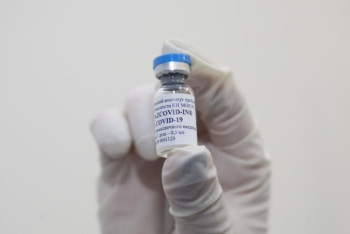

Еуропадағы бойкоттан кейін AstraZeneca вакцинасының атауы ауысып кетті

Нұр-Сұлтан, BAQ.KZ. AstraZeneca ағылшын-швед фармацевтикалық компаниясы Оксфорд университетімен бірлесіп жасалған коронавирусқа қарсы AZD1222 вакцинасының атауын ауыстырып тастады. Енді ол Vaxzevria деп аталады.

Qazcovid-in вакцинасының бір дозасының құны қанша?

Нұр-Сұлтан, BAQ.KZ тілшісі. Бұл туралы бүгін ҚР Президенті жанындағы Орталық коммуникациялар қызметі алаңында «Qazcovid-in қазақстандық вакцинасы туралы» тақырыбы аясында өткен онлайн брифинг кезінде Биологиялық қауіпсіздік проблемалары ғылыми-зерттеу институтының бас директоры Күнсұлу Закарья айтты.

Вакцинациялауға бөлінген 50 млрд теңгенің қанша бөлігі отандық вакцинаға бағытталған?

Нұр-Сұлтан, BAQ.KZ тілшісі. Бұл туралы бүгін ҚР Президенті жанындағы Орталық коммуникациялар қызметі алаңында «Qazcovid-in қазақстандық вакцинасы туралы» тақырыбы аясында өткен онлайн брифинг кезінде ҚР БҒМ ғылым комитетінің төрайымы Жанна Құрманғалиева айтты.

Qazcovid-in-нен бөлек тағы 4 вакцина өндірілуде

Нұр-Сұлтан, BAQ.KZ тілшісі. Бұл туралы бүгін ҚР Президенті жанындағы Орталық коммуникациялар қызметі алаңында «Qazcovid-in қазақстандық вакцинасы туралы» тақырыбы аясында өткен онлайн брифинг кезінде Биологиялық қауіпсіздік проблемалары ғылыми-зерттеу институтының бас директоры Күнсұлу Закарья айтты.

Қазақстандықтар отандық вакцинаны сәуірдің соңында алады

Нұр-Сұлтан, BAQ.KZ тілшісі. Бұл туралы бүгін ҚР Президенті жанындағы Орталық коммуникациялар қызметі алаңында «Qazcovid-in қазақстандық вакцинасы туралы» тақырыбы аясында өткен онлайн брифинг кезінде Биологиялық қауіпсіздік проблемалары ғылыми-зерттеу институтының бас директоры Күнсұлу Закарья айтты.

Президент күтіп отырған отандық вакцина қашан дайын болады?

Нұр-Сұлтан, BAQ.KZ тілшісі. Бұл туралы бүгін ҚР Президенті жанындағы Орталық коммуникациялар қызметі алаңында «Qazcovid-in қазақстандық вакцинасы туралы» тақырыбы аясында өткен онлайн брифинг кезінде Биологиялық қауіпсіздік проблемалары ғылыми-зерттеу институтының бас директоры Күнсұлу Закарья айтты.

QazVac коронавирустың жаңа штамдарына қаншалықты қауқарлы?

Нұр-Сұлтан, BAQ.KZ тілшісі. Бұл туралы бүгін ҚР Президенті жанындағы Орталық коммуникациялар қызметі алаңында «Qazcovid-in қазақстандық вакцинасы туралы» тақырыбы аясында өткен онлайн брифинг кезінде Биологиялық қауіпсіздік проблемалары ғылыми-зерттеу институтының бас директоры Күнсұлу Закарья айтты.